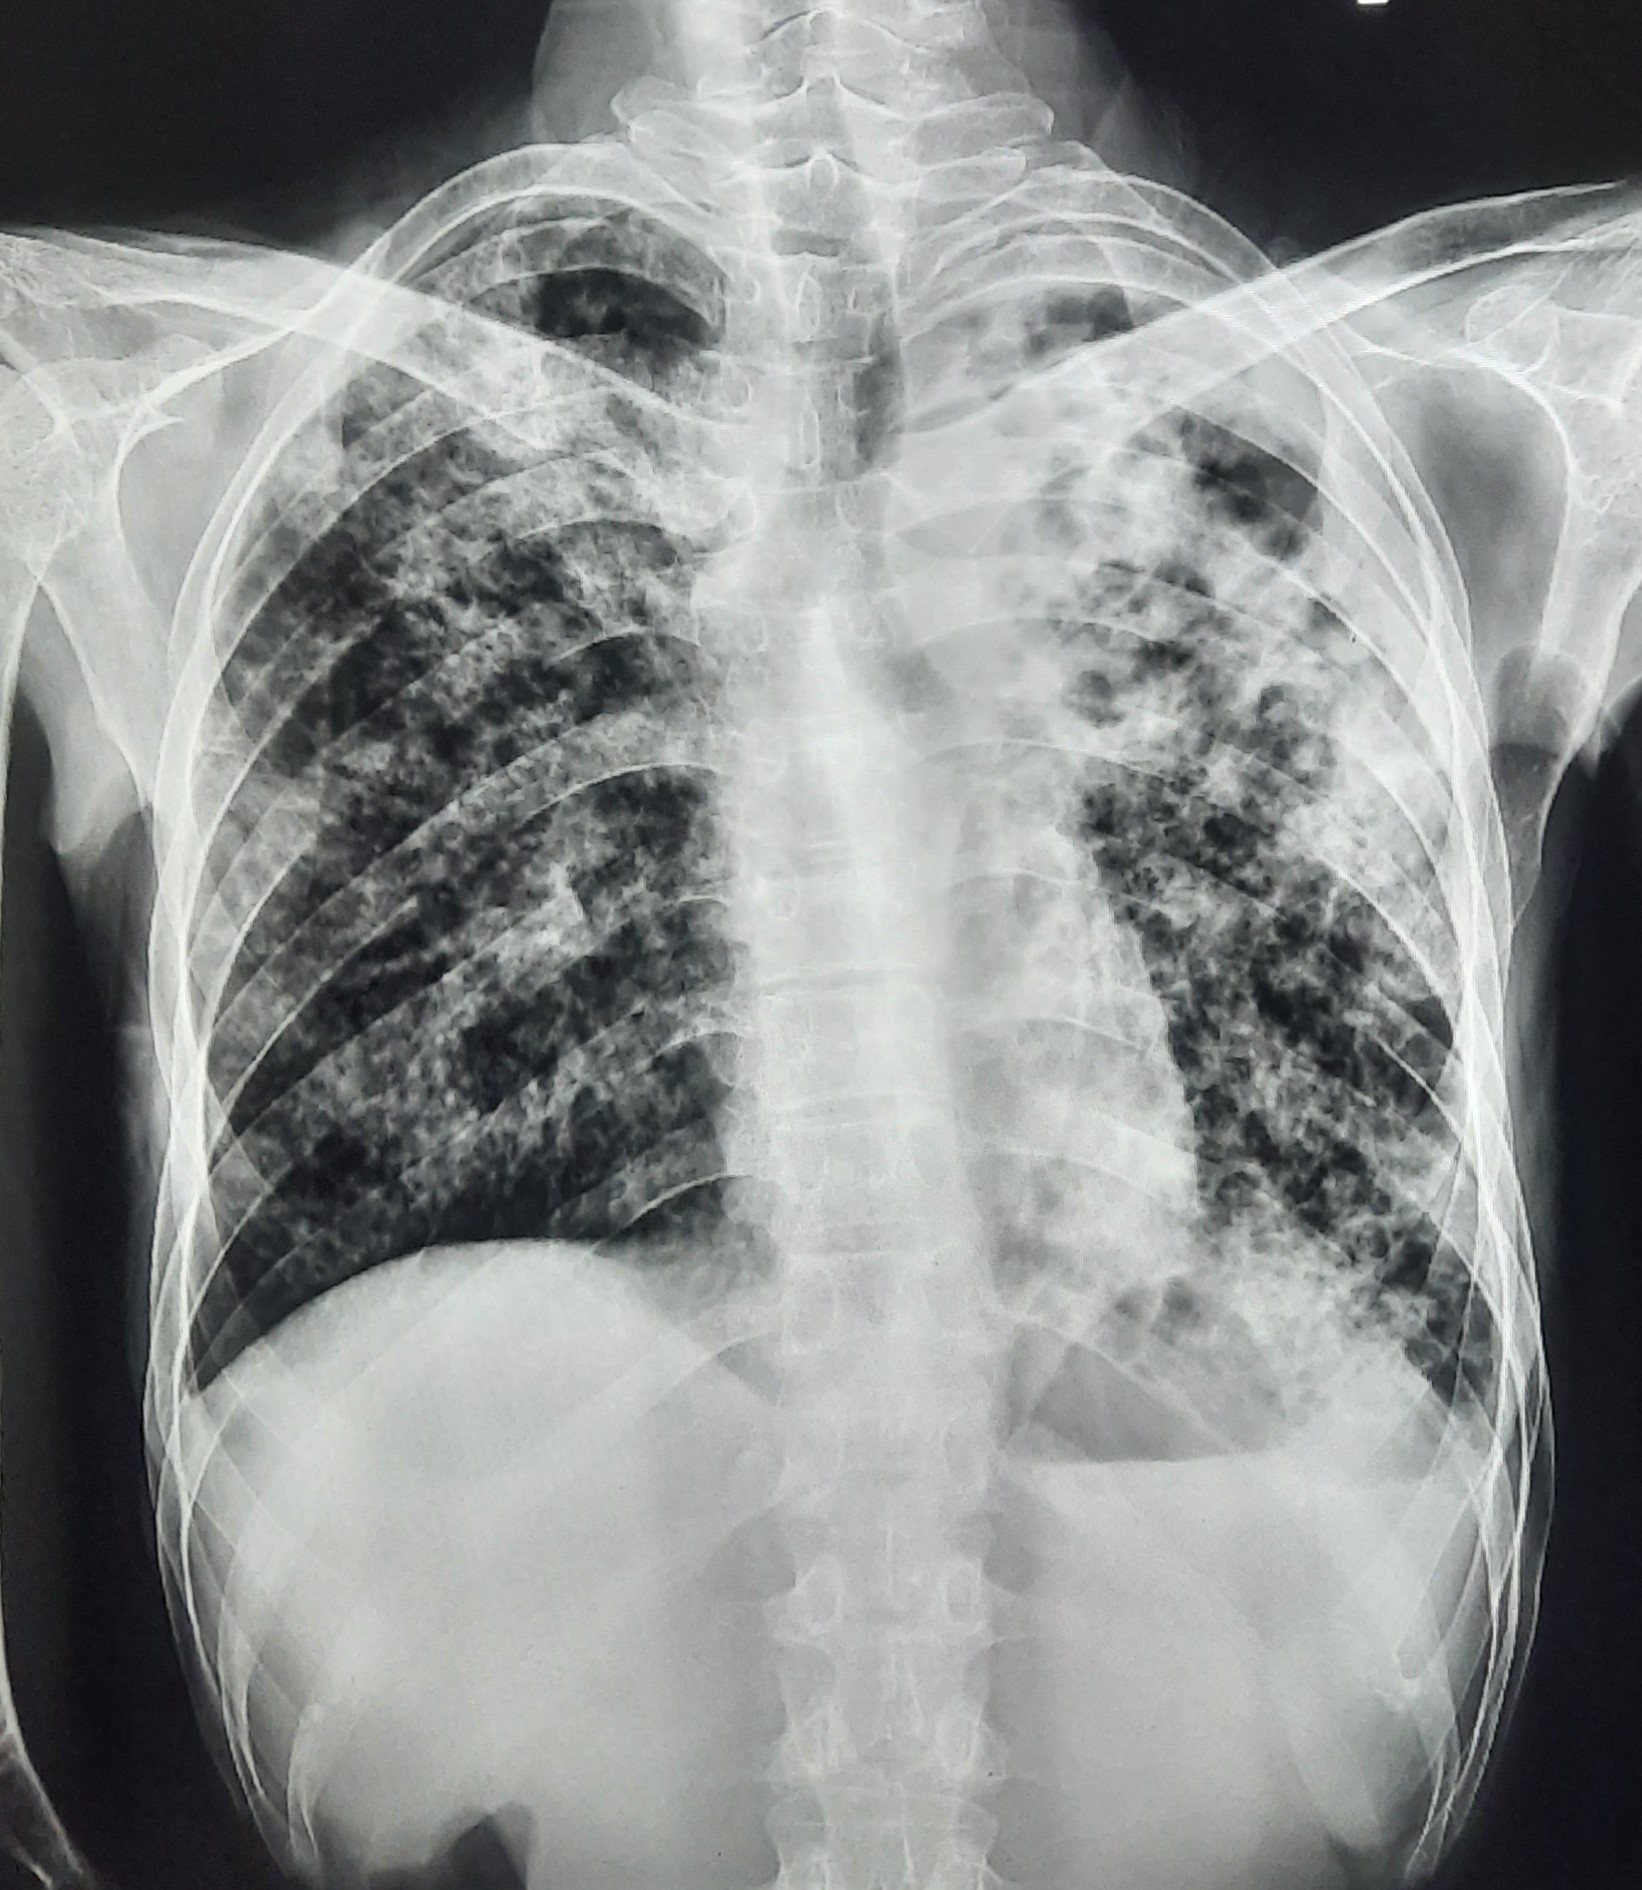

| 84 | IGGMC, Nagpur, Nagpur | P2 | 29-4388 | Dipak Panchbudhe | Consent taken on Paper | 33 Yrs. |

Provisional Diag : Pulmonary Tuberculosis Reactivation ?

Final Diag : Pulmonary Tuberculosis |

TB Case (Confirmed) | Bilateral multiple ill-defined alveolar opacity present, Left Sided Upper Zone Fibro Cavitary Lesion Present | Abnormality visible on x-ray |